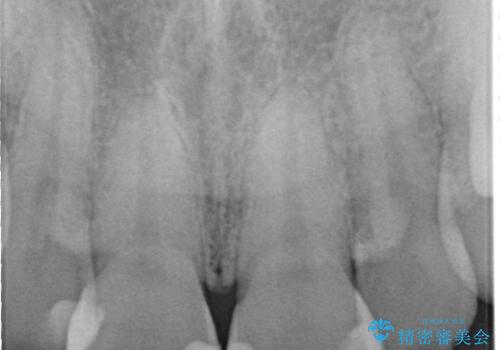

- 定期的に当院に通院されている患者様ですが、前歯が欠けてしまい困っているとのことで来院されました。その日は応急でレジン充填を行いましたが、上下顎前歯の当たりが強くまた同じように欠けてしまう可能性が高いと考え、セラミッククラウンにて修復した一例です。前歯一歯の色合わせは非常に難しく、特に周囲の歯に模様がある場合難易度が上がります。そのため、今回は当院のセラミッククラウンの中で最もランクの高いものを選択し、非常に綺麗に仕上げることができました。